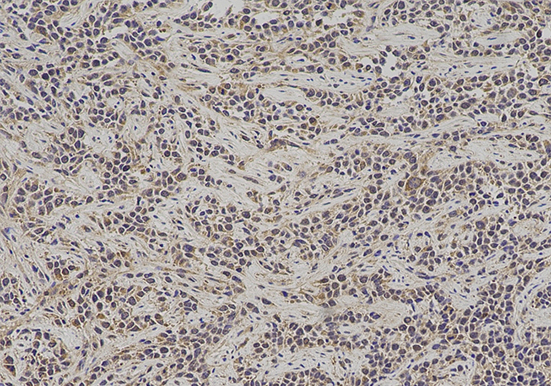

免疫组化

技术原理免疫组化,是应用免疫学基本原理——抗原抗体反应,即抗原与抗体特异性结合的原理,通过化学反应使标记抗体的显色剂(荧光素、酶、金属离子、同位素)显色来确定组织···